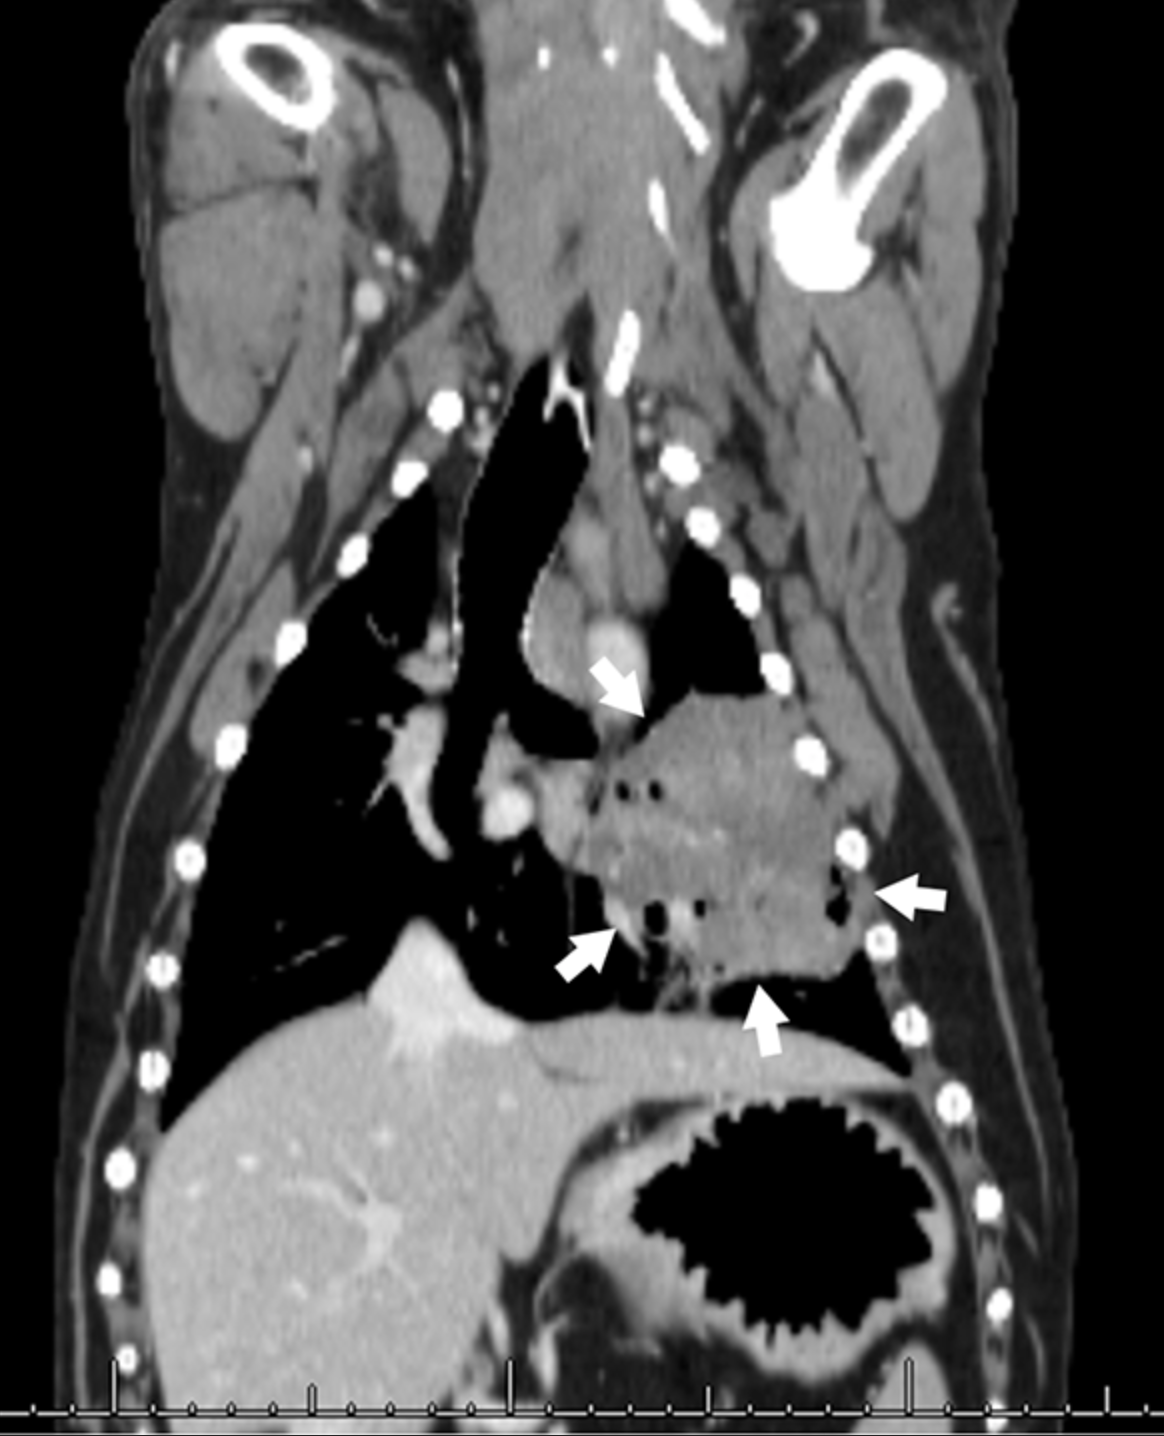

La metástasis en los ganglios linfáticos se identificó mediante histopatología quirúrgica en algunos perros que tenían ganglios linfáticos radiológicamente normales según las imágenes de TC. Esto resalta la importancia de la extirpación quirúrgica de los ganglios linfáticos cuando sea posible, a pesar de que la anatomía es ocasionalmente desafiante e independientemente de los hallazgos de las imágenes preoperatorias. Se justifica la investigación adicional sobre el impacto a largo plazo de la metástasis en los ganglios linfáticos en perros con tumores pulmonares primarios.